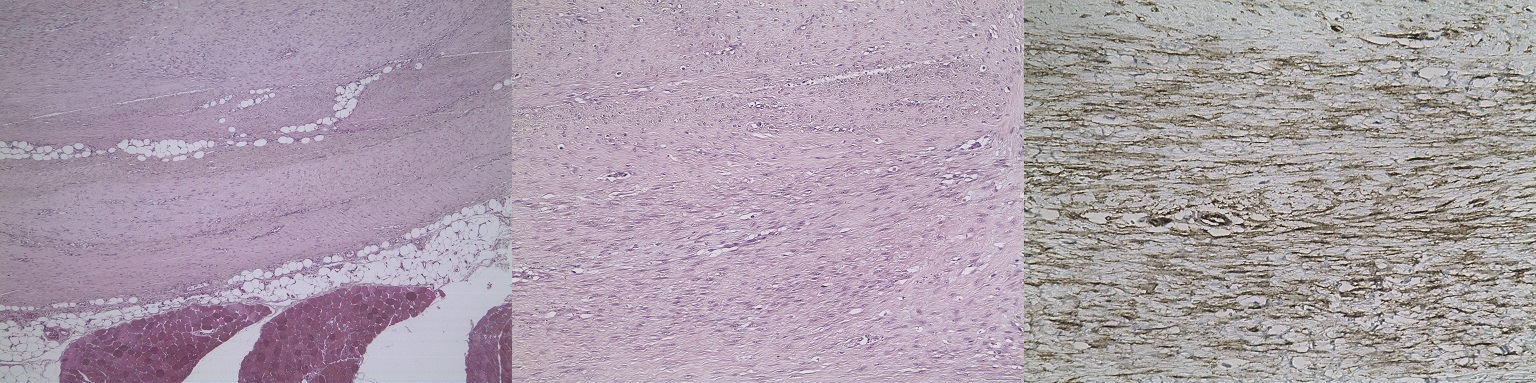

Η εργασία παρουσιάστηκε στο 33ο Πανελλήνιο συνέδριο Χειρουργικής & International surgical forum που έλαβε χώρα στην Αθήνα από 11-15 Νοεμβρίου 2023. Σκοπός της η περιγραφή της διάγνωσης και αντιμετώπισης της εξωκοιλιακής δεσμοειδούς ινωμάτωσης. Πρόκειται για σπάνιο όγκο ινώδους ιστού με χαμηλόβαθμη κακοήθεια και υψηλή πιθανότητα υποτροπής (25-77%). Σποραδική (85%): εξωκοιλιακή (60%) και κοιλιακού τοιχώματος (25%) και μη σποραδική: ενδοκοιλιακή – μεσεντέριο (15%). Συνήθης ηλικία εμφάνισης 35-40 ετών, 70% γυναίκες. Επεκτείνεται τοπικά, όχι απομακρυσμένες μεταστάσεις. Ενοχοποιούνται τραυματισμοί, διαταραχές οιστρογόνων, χρωμοσωμικές ανωμαλίες γονιδίου κατενίνης b-1 (CTNNB1) και σχέση με σύνδρομα οικογενούς πολυποδίασης και Gardner. Ο εξωκοιλιακός δεσμοειδής όγκος εκδηλώνεται συνήθως στο μυ, την περιτονία και την απονεύρωσή του στα κάτω άκρα, ως ψηλαφητή μάζα, με πόνο, περιορισμό κίνησης στο βάδισμα και παραισθησία. Προτεινόμενη μέθοδος απεικόνισης η MRI. Διάγνωση με core biopsy, ανοσοϊστοχημικά εκφράζεται με (+) υποδοχείς ανδρογόνων και β-οιστρογόνων, 80% παρουσιάζει ανώμαλο πυρηνικό εντοπισμό β-κατενίνης. Επιλογές θεραπείας: στρατηγική χειρουργικής watch and wait, επεμβατική radiofrequency ablation και cryoablation υπό CT, ακτινοθεραπεία, χημειοθεραπεία με αναστολείς τυροσίνης κινάσης (TKIS) ή μεθοτρεξάτη+βινπλαστίνη σε συνδυασμό με δοξορουμπικίνη, βινκριστίνη, ακτινομυκίνη και κυκλοφωσφαμίδη. Φαρμακευτική αγωγή με αντιοιστρογόνα και ΜΣΑΦ. Χειρότερη πρόγνωση αν ηλικία <37, μέγεθος όγκου >7 cm. Η θεραπεία του δεσμοειδούς όγκου αποτελεί ακόμη πρόκληση. Προκρίνεται παρακολούθηση χωρίς χειρουργική για 1-2 χρόνια και προτείνεται χημειοθεραπεία με TKIs όταν μεγαλώνει ο όγκος και δίνει συμπτώματα.